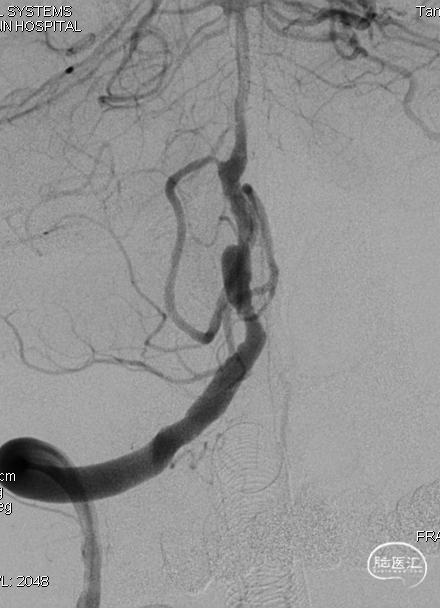

DSA示双侧椎动脉V4段狭窄,右侧为著且合并梭形动脉瘤。

逐步释放Pipeline(3.00*30)。

支架完全释放,微导丝“按摩”支架。

术后即刻DSA。

术后即刻稀释造影:“拉直”可见支架贴壁良好。